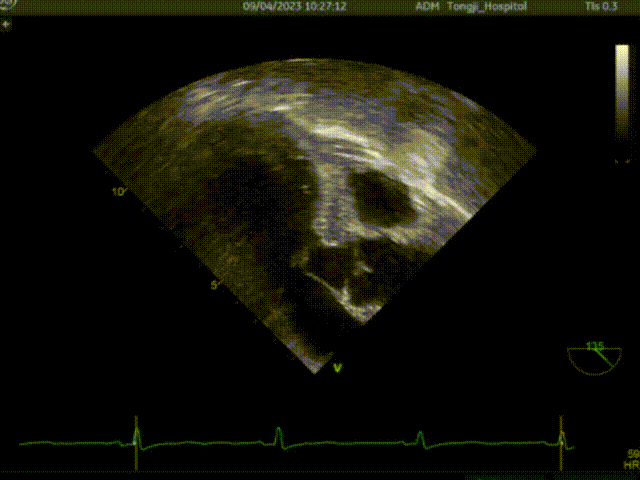

一、经心尖不停跳室间隔切除术

共切除3刀

二、行经心尖介入二尖瓣夹合手术ValveClamp

ValveClamp抓捕瓣叶并收入闭合环内

该患者为老年女性,左室流出道压差134mmHg,二尖瓣前后叶冗长,即便切除了增厚的心肌组织,二尖瓣仍然可能存在反流,同时前叶冗长有阻挡流出道的风险,术前魏翔教授团队就治疗方案进行了充分的商议,最终提出使用两种来自中国原创的新器械(心肌旋切系统+ValveClamp),在同一切口下行不停跳魏氏心肌旋切术加经心尖介入二尖瓣夹合术。